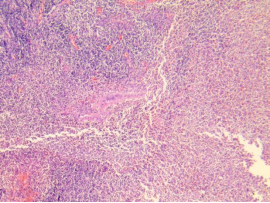

坏疽性阑尾炎

常为化脓性阑尾炎继续发展的结果,由于系膜炎症使阑尾静脉血栓形成,从而引起阑尾广泛出血梗死,阑尾各层广泛出血坏死和急性炎细胞浸润。肌层出血坏死严重者可引起穿孔。

黏膜及肌层坏死,浆膜下大量中性粒

细胞,伴坏死、出血